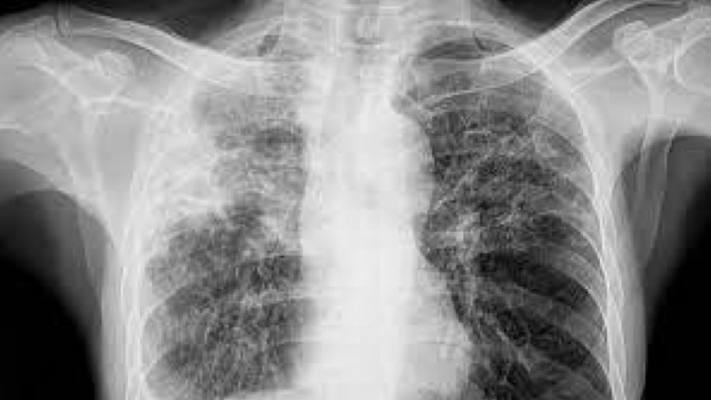

Portugal registou 1.536 casos de tuberculose em 2024, o valor mais baixo de sempre, segundo um relatório da Direção-Geral da Saúde, que mostra que entre os imigrantes a taxa é quase três vezes superior à média nacional.

O Relatório de Vigilância e Monitorização da Tuberculose em Portugal, divulgado no Dia Mundial da Tuberculose, confirma a tendência de descida da tuberculose no país, com uma taxa de notificação de 14,3 casos por 100 mil habitantes.